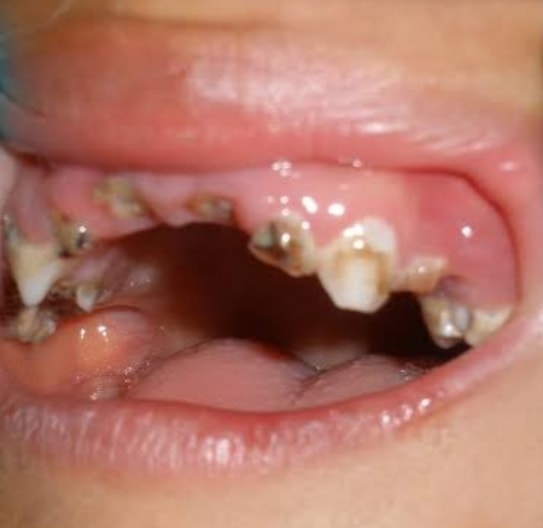

นายแพทย์ อารักษ วงศ์วรชาติ ผู้อำนวยการโรงพยาบาลสิชล จังหวัดนครศรีธรรมราช เผยแพร่ภาพและข้อความ ผ่านเฟสบุ๊กส่วนตัว โดยระบุว่า ผู้ป่วยเด็กชายอายุ 3 ขวบเศษ มาด้วยไข้ ปวดตาซ้าย ตาบวมแดงมาก ตาปิด มองเห็นรางๆ ตรวจในช่องปาก ฟันน้ำนมผุทั้งปาก

มารดา ญาติ ชอบหาอมยิ้มให้เด็กดูด จะได้ไม่ร้องกวน ไม่ค่อยได้แปรงฟัน ไม่ได้เข้าโรงเรียนอนุบาลหรือศูนย์เด็กเล็ก

เอกซเรย์คอมพิวเตอร์ใบหน้า พบมีหนองในไซนัสและเบ้าตา รากฟันบนต้องผ่าตัดถอนฟันทั้งปากที่ผุ ระบายหนองออก ให้ยาต้านเชื้อทางเส้นเลือดอยู่หลายวัน